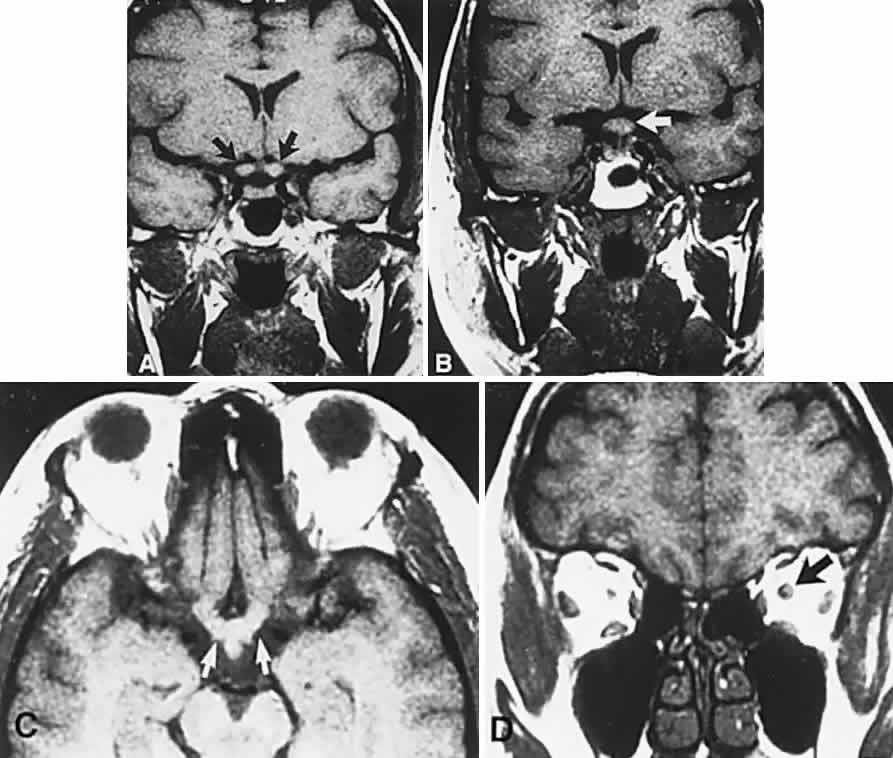

Fig. 3. Neuroimaging of pituitary adenomas. A. Axial computed tomography (CT) section shows a round tumor mass filling the suprasellar cistern; ring enhancement (arrows) indicates subcapsular hemorrhage. B. Contrast-enhanced coronal CT section through a large invasive adenoma. Note encasement of the carotid artery (arrows) and the position of the middle cerebral artery above (arrowheads). C. Axial CT section shows lateral expansion into the cavernous sinuses (white arrows) and a necrotic cyst (black arrow). D. Subfrontal superior extent of the mass. Note the middle cerebral arteries. E. Magnetic resonance imaging of a large lobulated prolactinoma, with suprasellar extension. Note the distortion of the third ventricle (open arrows) and extension toward the temporal lobe (long arrow); the tumor has not involved the sphenoidal sinus (s). F. Chiasm (arrowheads) is draped on the superior surface of the tumor (TR, 550 milliseconds; TE, 26 milliseconds). G. Sagittal section shows suprasellar growth with the chiasm above (arrowheads); the sella (arrows) and sphenoidal sinus (s) are normal (TR, 850 milliseconds; TE, 26 milliseconds). H. Hyperintense signal (TR, 2000 milliseconds; TE, 60 milliseconds) indicates the partial cystic character. Sagittal (I) and axial (J) sections with head tilt to the right, in case of a large cystic adenoma with an interface level between newer blood (white arrow) and older blood (black arrow) (TR, 800 milliseconds; TE, 30 milliseconds). K. Signal difference is intensified (TR, 2100 milliseconds; TE, 80 milliseconds). L. Hemorrhage (bright signal, arrow) in a pituitary adenoma with headache and bitemporal field depressions. M. Without interventions, 2-month follow-up showed spontaneous involution, with normal pituitary gland (arrow), stalk, and chiasm.